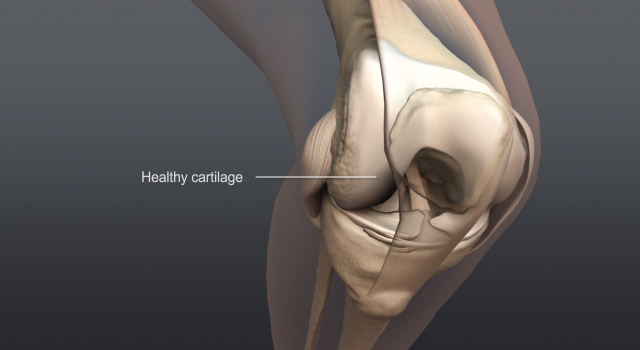

Management of Osteoarthritis of the Knee (Non-Arthroplasty)

Evidence-Based Clinical Practice GuidelineAdopted by:The American Academy of Orthopaedic Surgeons Board of DirectorsAugust 31, 2021 This clinical practice guideline (CPG) was developed by a physician volunteer clinical practice guidelinedevelopment group based on a formal systematic review of the available scientific and clinicalinformation and accepted approaches to...